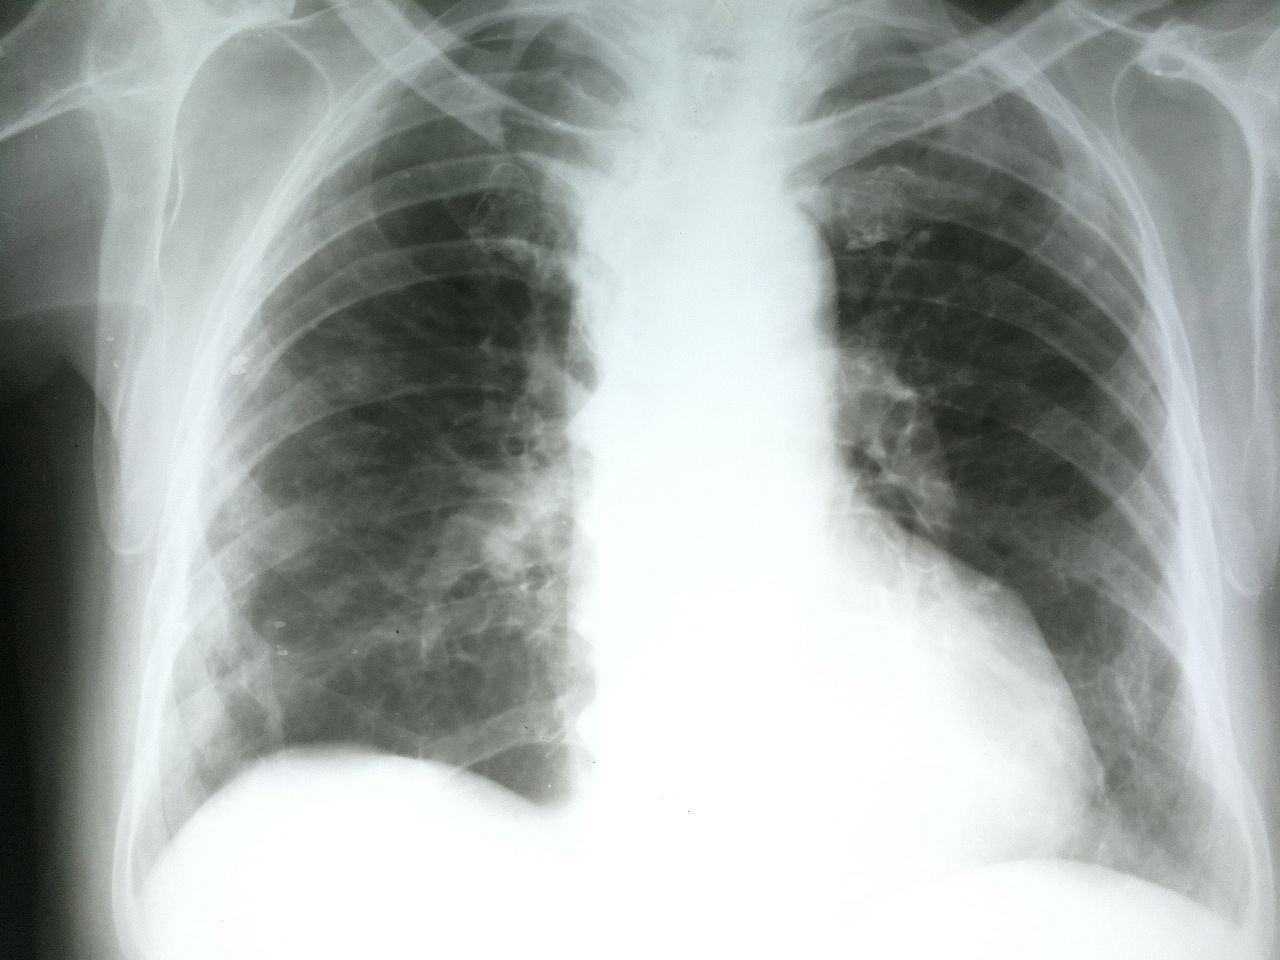

Переслано от Сергей Чибиряк...

Бабушка, 74 года, температуры и кашля нету, жалобы только на одышку и говорит что имеет проблемы с сердцем, аритмии. Подскажите как правильно описать (застойные явления, пневмосклероз)?

Сергей Чибиряк

Переслано от Сергей Чибиряк

необходима тест на корону и КТ

Билол Халимов

А в заключении писать пневмония?

полисегментарную